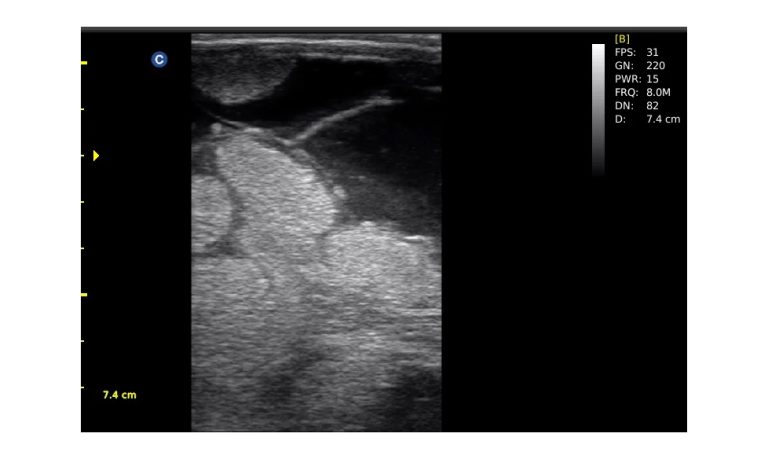

Ultrasound

Wide range of Ultrasound machines that suites a variety of applications from abdominal to rectal scans, we take in consideration how the world is moving towards mobility and mobile applications.

SonoScape Pro Pet E11

Smart Imaging

Introducing the first portable ultrasound with the C-Field+TM platform, redefining diagnostic imaging. Designed for veterinarians, it delivers unmatched clarity, ultra-fast processing, and seamless adaptability for all species. Experience Smart Imaging, Heartfelt Care—anywhere.

Equipped with cutting-edge veterinary software and optimized workflows, it embodies our commitment to Smart Imaging, Heartfelt Care – Wherever Their Journey Leads, with unparalleled performance and adaptability, this innovative system empowers veterinarians to provide exceptional care across all diagnostic applications,

Esaote MyLab Sigma; So Fast, So Easy

Esaote’s new MyLab™SigmaVET is the smart, portable solution that allows use of an ultrasound whenever a quick and complete diagnosis is required.

EBIT50/60 VET

All the power you need

The EBit provides all the power you need for today´s challenging clinical environment, yet remain ultra-portable, ultra-affordable. With its cutting-edge imaging technologies, precise and intuitive workflow, ergonomic and eco-friendly design, versatile transducers for all applications from top to toe, we firmly believe the EBit to be the very best portable ultrasound in its class today.

ECO5 VET

Ultra-Portable, Ultra- Affordable, Color doppler

The multi-purpose user presets, comprehensive measurement & report system, built-in EasyView image achieve system, quick image storage / retrieve / transfer, one-button direct print, make the complete workflow better than what you can dream of.